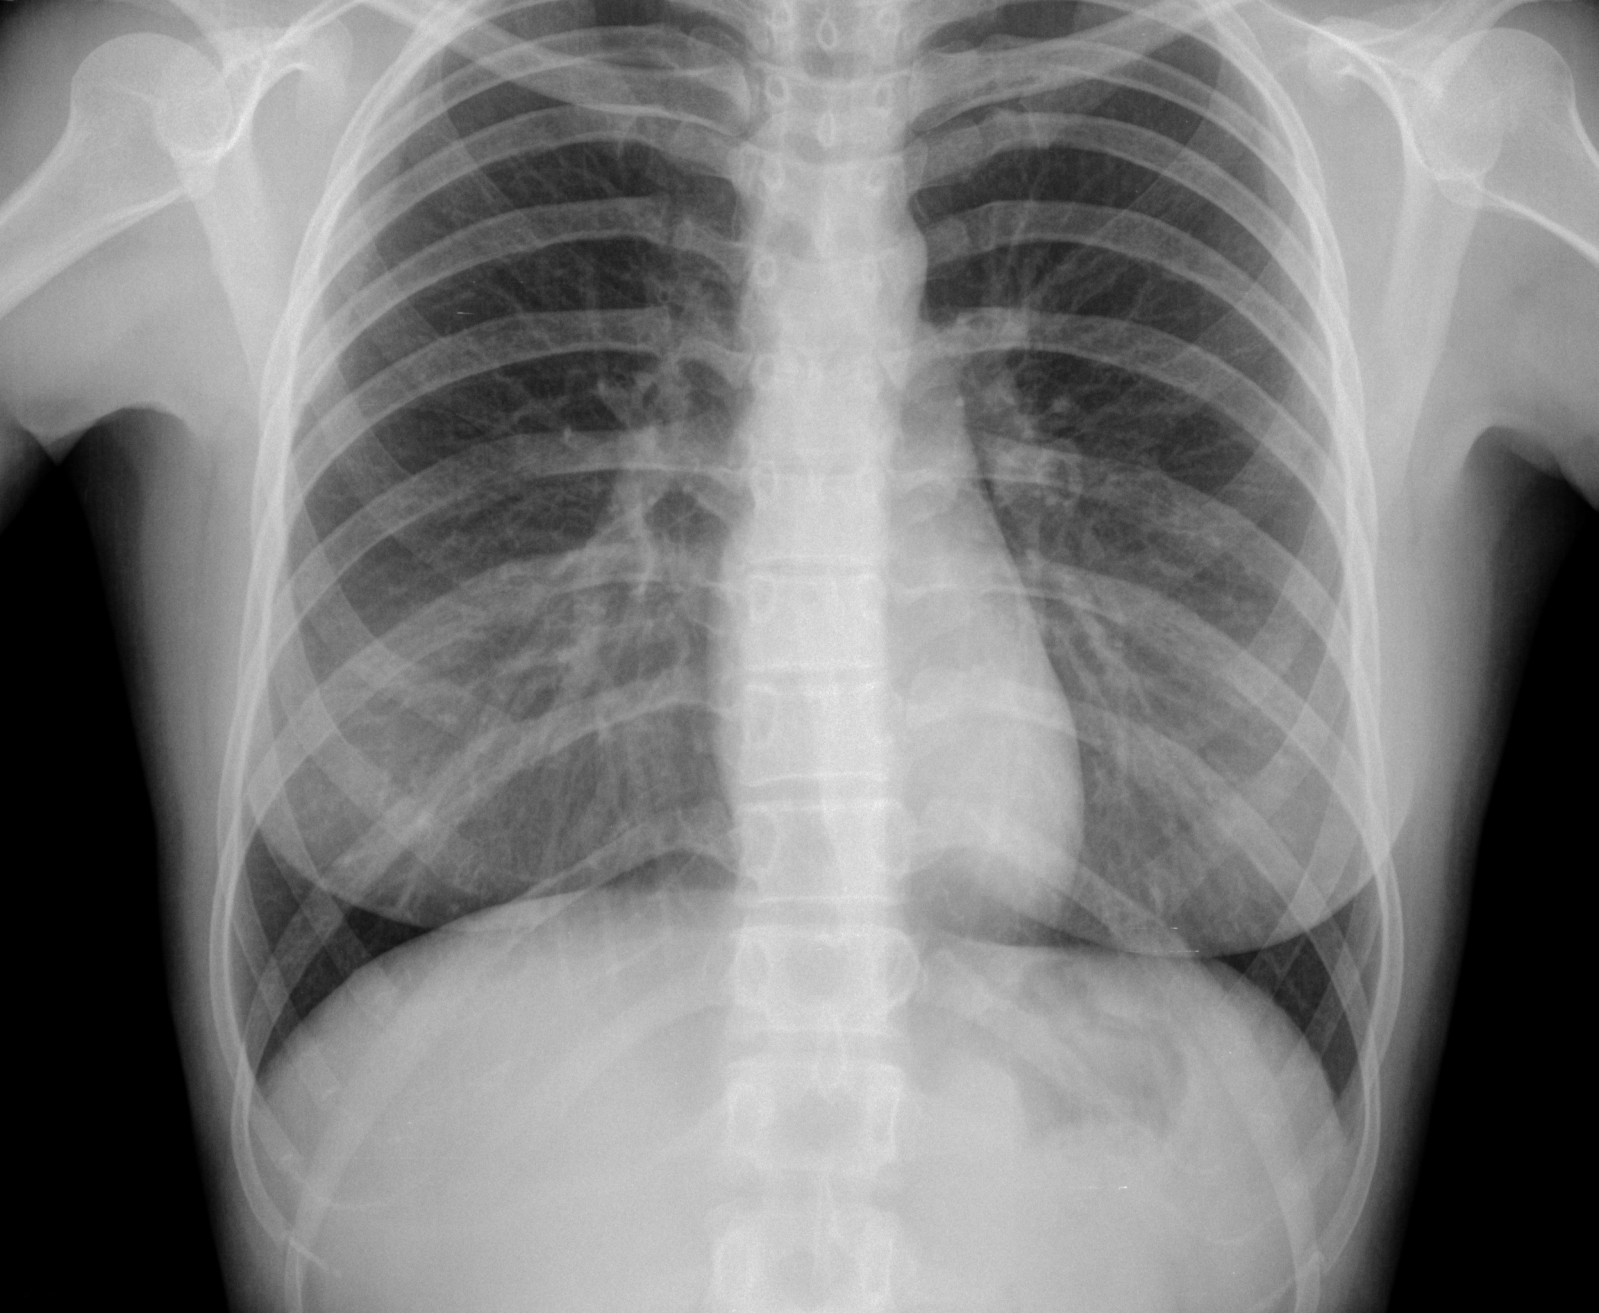

Ракът на белия дроб представлява растеж на променени клетки в белите дробове, които се делят много по-бързо от здравите клетки и групирайки се образуват тумор. Повечето типове рак на белия дроб нарастват бавно и често минава дълго време преди да се проявят симптомите. Тъй като е обичайно ракът на белия дроб да метастазира доста рано, в повечето случаи той бива диагностициран едва, когато ракови клетки са се появили на други места в организма.

Има два основни вида рак на белия дроб - дребноклетъчен и недребноклетъчен рак на белия дроб (НДКРБД), въз основа на това как изглеждат раковите клетки, видяни под микроскоп. НДКРБД съставлява около 80% от всички случаи на рак на белия дроб. Основните симптоми на рака на белия дроб са: кашлица, която не изчезва; задух или хриптене по време на дейности, които преди са извършвани лесно; пресипнал глас; отделяне на кръв при кашляне; загуба на апетит или нежелана загуба на тегло, без видима причина; повтарящи се пристъпи на бронхит; болки в гърдите, гърба и ръцете.